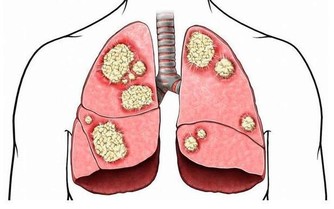

9. 脊柱腫瘤

大多數背痛病例不是由脊柱腫瘤引起的,但背痛是90%脊柱腫瘤患者的症狀,脊柱瘤可能影響脊柱或脊柱上的任何結構。疼痛的位置取決於生長腫瘤的脊柱位置。脊髓腫瘤的常見症狀包括腰部或背部疼痛,疼痛通常出現在夜間,並且隨著身體的活動而惡化。如果腫瘤位於脊柱的中間或下部,可能會出現腿部麻木或肌肉無力,以及腸功能損失的情況。

10. 癌症

如果腰痛不能精確定位,可能是由於內臟癌症,如胰腺、十二指腸、結腸、子宮、子宮頸和卵巢等。其症狀就包括背部疼痛,即使充分休息也不能緩解,並且夜間疼得最厲害。這種非機械性的背部疼痛,若藥物治療和姿勢改善都不能使其好轉,就需要去看醫生了。